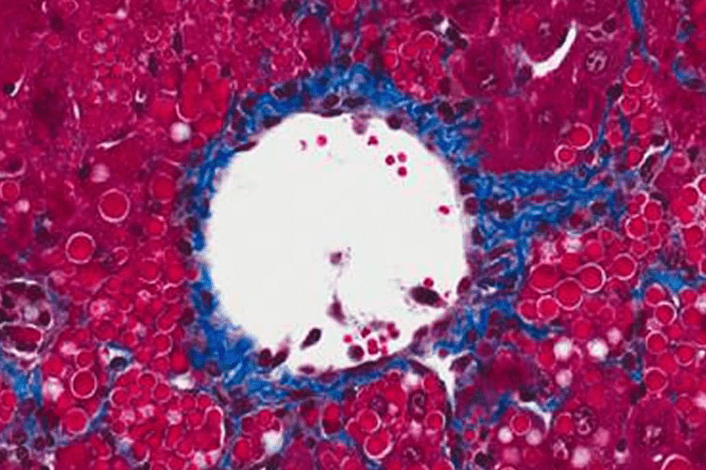

close up of slide of cell

Alpha-1 Research at UMass Chan Medical School

Find out about the Alpha-1 research that is being conducted at UMass Chan Medical School and how we are trying to make a difference.